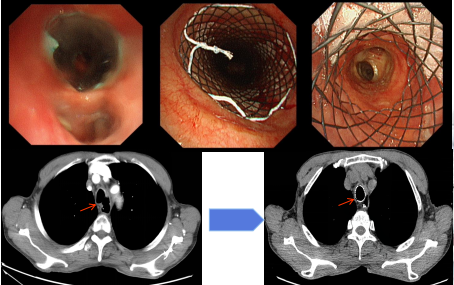

Y型支架置入术

目前不仅开展常规、无痛气管镜检查,而且开展了经支气管针吸活检术(TBNA)、超声内镜引导下经支气管针吸活检术(EBUS-TBNA)、经支气管镜肺组织活检术(TBLB)、硬镜下气道内肿物开通术(激光、氩气、电切、冻切等)、气道瘢痕狭窄切开松解术、支气管异物取出术、气道狭窄球囊扩张术及冷冻术,硬镜下气道支架植入术,胸膜瘘修补术、内科胸腔镜、小儿支气管镜、快速现场细胞学评价等呼吸介入领域的高难度技术,其中多项呼吸内镜下介入手术填补了内蒙古自治区的空白。短短5年时间,气管镜总例数已达8000余例,三、四级手术达1900余例,处于内蒙古自治区领先水平。在业务技术上,不断拓展提高,2023年开展LungPro导航引导下肺外周病灶气道内活检术,2024年放置Y型支架3例,并开展光动力治疗,标志着我基地呼吸介入技术再上新台阶。